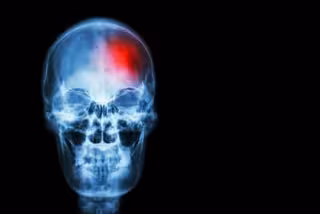

Archivo - Ictus

Archivo - Ictus - STOCKDEVIL/ ICTUS - Archivo

El ictus es una emergencia médica que se produce cuando un vaso sanguíneo del cerebro se bloquea o revienta, impidiendo que el oxígeno y los nutrientes lleguen al cerebro. Es una de las principales causas de discapacidad a largo plazo. El tratamiento rápido es fundamental para evitar daños cerebrales o la muerte, por lo que es importante reconocer los signos de advertencia del ictus y la actuación correcta.